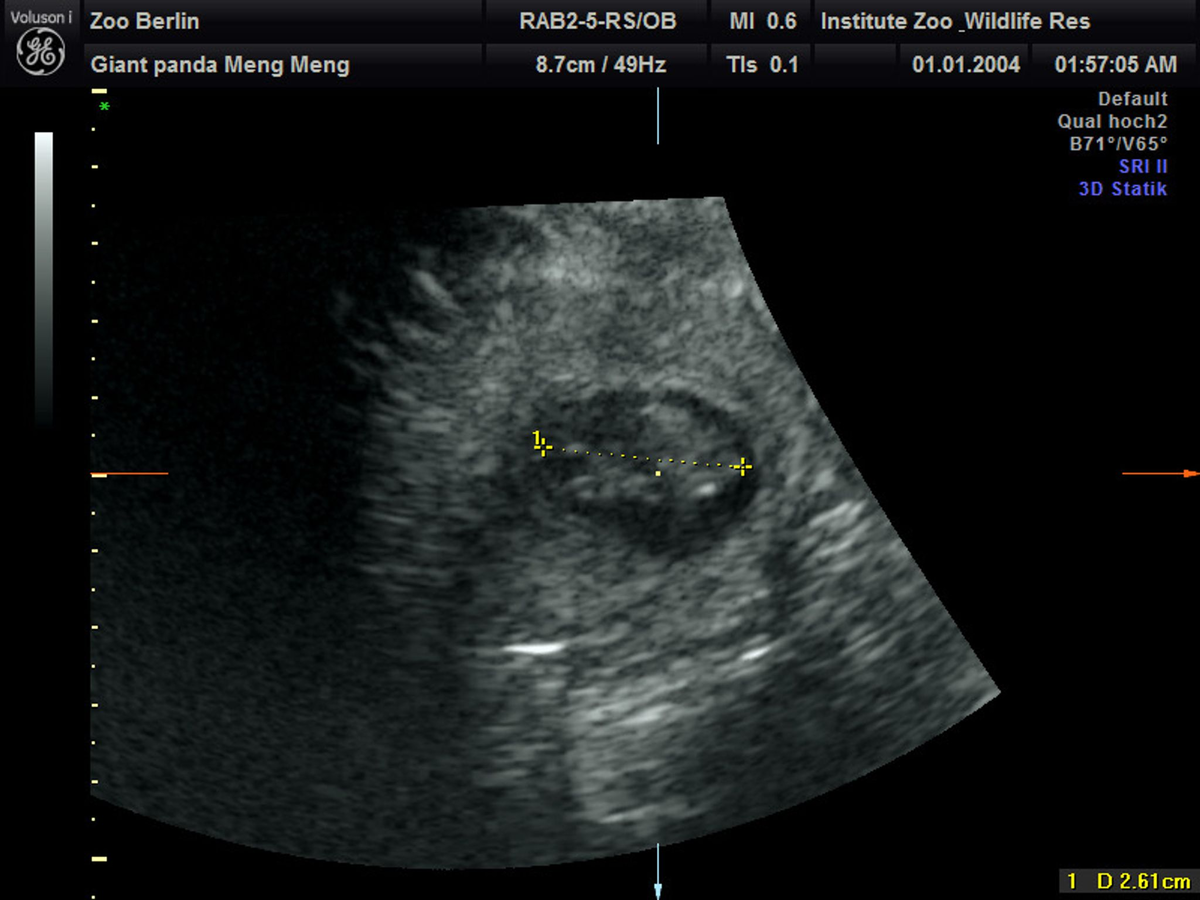

13.08.2024 - 08:49:13 | dpa.deNach fünf Jahren wird im Berliner Zoo wieder Panda-Nachwuchs erwartet. Das Pandaweibchen Meng Meng ist mit zwei Jungtieren trächtig, wie der Zoo am Dienstag mitteilte. «Nach Wochen gespannten Hoffens brach am Sonntagmorgen im Panda Garden des Zoo Berlin ein kleiner Jubel aus. Erst war ein Herzschlag, kurz darauf sogar ein zweiter auf dem Ultraschallgerät zu erkennen.» Die Pandababys seien etwa 2,5 Zentimeter groß und müssten bis zur Geburt jetzt noch ordentlich wachsen.

Kühles Ultraschall-Gel auf Panda-Bauch

Bei Ultraschall-Untersuchungen auf eine mögliche Schwangerschaft habe sich das Pandaweibchen zuletzt nicht besonders kooperativ gezeigt. Am Sonntag sei es aber gut gelaufen. «Trotz sichtlichen Bauchkneifens ließ sich Meng Meng überzeugen, in den aufrechten Stand zu kommen und das kühle Ultraschall-Gel sowie die Untersuchung mit der Ultraschall-Sonde zu akzeptieren», teilte Thomas Hildebrandt, Leiter der Abteilung für Reproduktionsmanagement am Leibniz-Institut für Zoo- und Wildtierforschung, mit. Die Untersuchung im Stehen habe schließlich die freudige Nachricht gebracht, dass Meng Meng trächtig sei.

Die Freude im Team sei riesig gewesen, weil es schon einige erfolglose Ultraschallversuche gegeben habe, sagte die Zootierärztin Franziska Sutter, die ebenfalls an der Untersuchung beteiligt war. «Bei aller Begeisterung müssen wir uns darüber im Klaren sein, dass das ein sehr frühes Stadium der Trächtigkeit ist und eine sogenannte Resorption – also ein Absterben - des Embryos zu diesem Zeitpunkt noch möglich ist.»